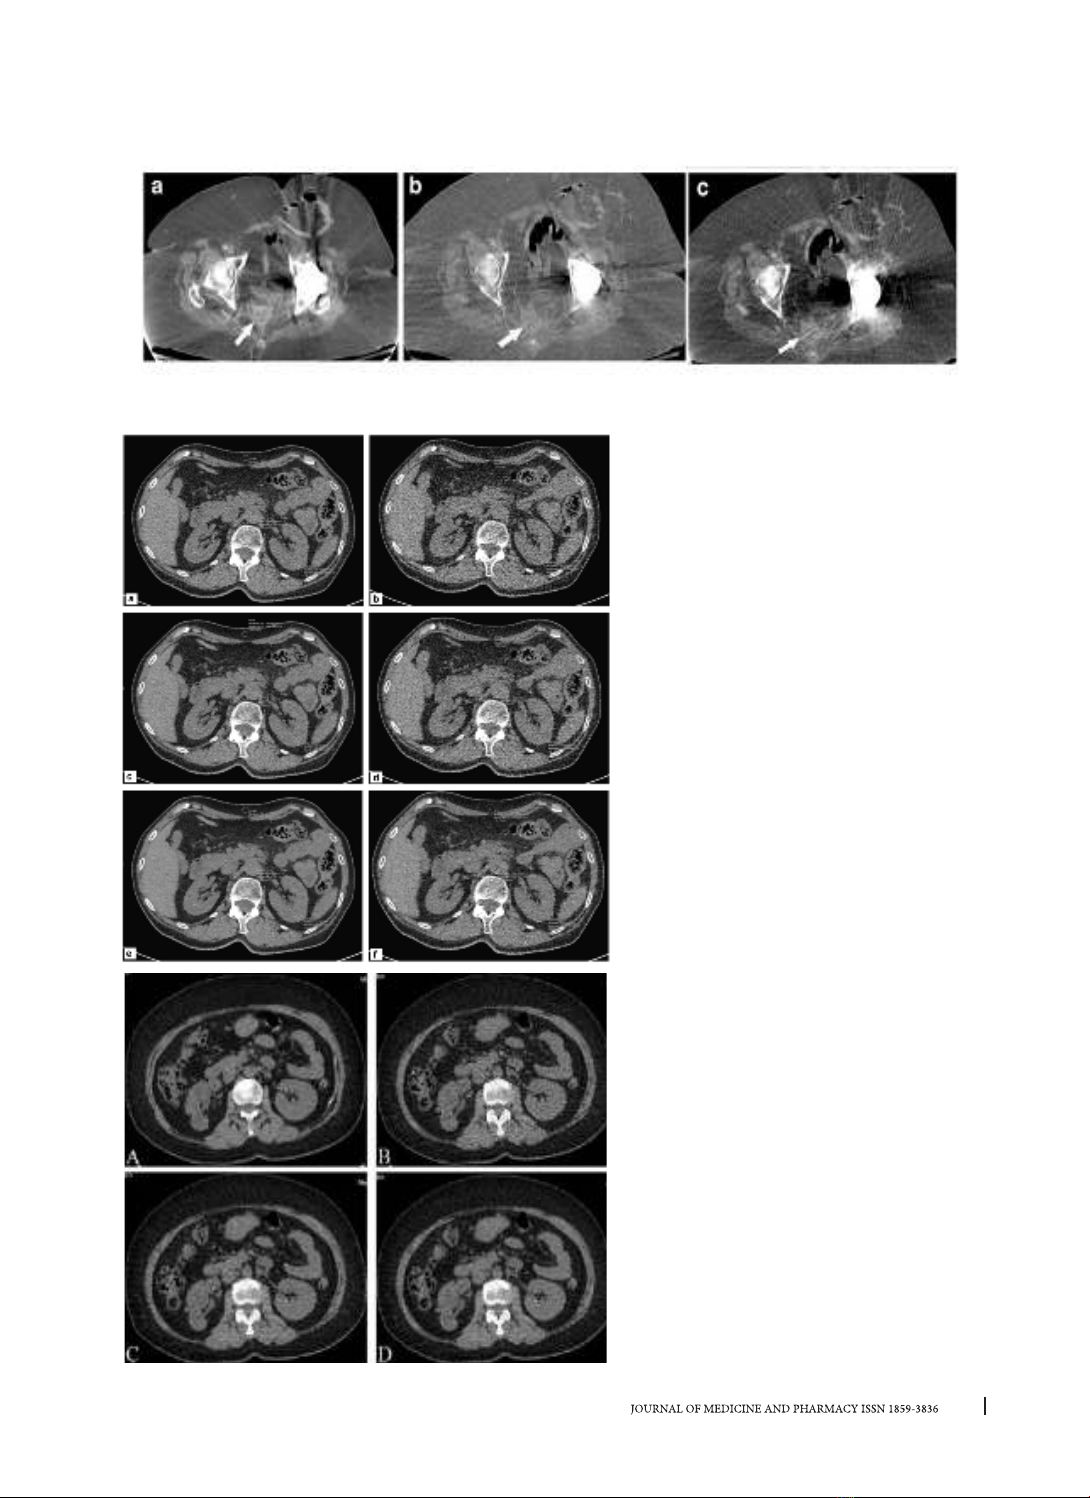

Hình 4. a, CT-FBP (20 mSv); b, LDCT-MBIR và c, LDCT–FBP (1,8 mSv). LDCT với IR cho thấy hiện thị tốt tổn

thương (mũi tên màu trắng) và khắc phục treak artifacts (hình b) [18].

Hình 5. Hình ảnh axial với FBP, Safire

mức 2/5 và Safire mức 5/5 của một bệnh

nhân với giảm 30% liều (a, c, e) và giảm

70% liều (b, d, f). Hình ảnh càng mịn hơn

khi tăng mức từ Safire 2/5 lên 5/5). Tỷ lệ

tín hiệu trên nhiễu (SNR) và tỷ lệ tương

phản trên nhiễu (CNR) tương đương giữa

Safire 2/5 ở 30% (c) và Safire 5/5 ở 70% (f)

khi so sánh ở 4 ROI tại thận trái, mỡ, động

mạch chủ bụng và cơ thắt lưng chậu [5].

Hình 6. Một bệnh nhân nam 50 tuổi với

sỏi nhỏ thận trái, kích thước 1,8 mm x 1,6

mm x 1,7 mm.

(A) Thăm khám thường quy với thuật toán

FBP (B) Thăm khám giảm liều với FBP; (C)

Thăm khám liều thấp với 60% ASIR; (D)

Thăm khám liều thấp với 80% ASIR. Chất

lượng hình ảnh thấp ở hình B, và tương tự

nhau ở hình A và D [21].